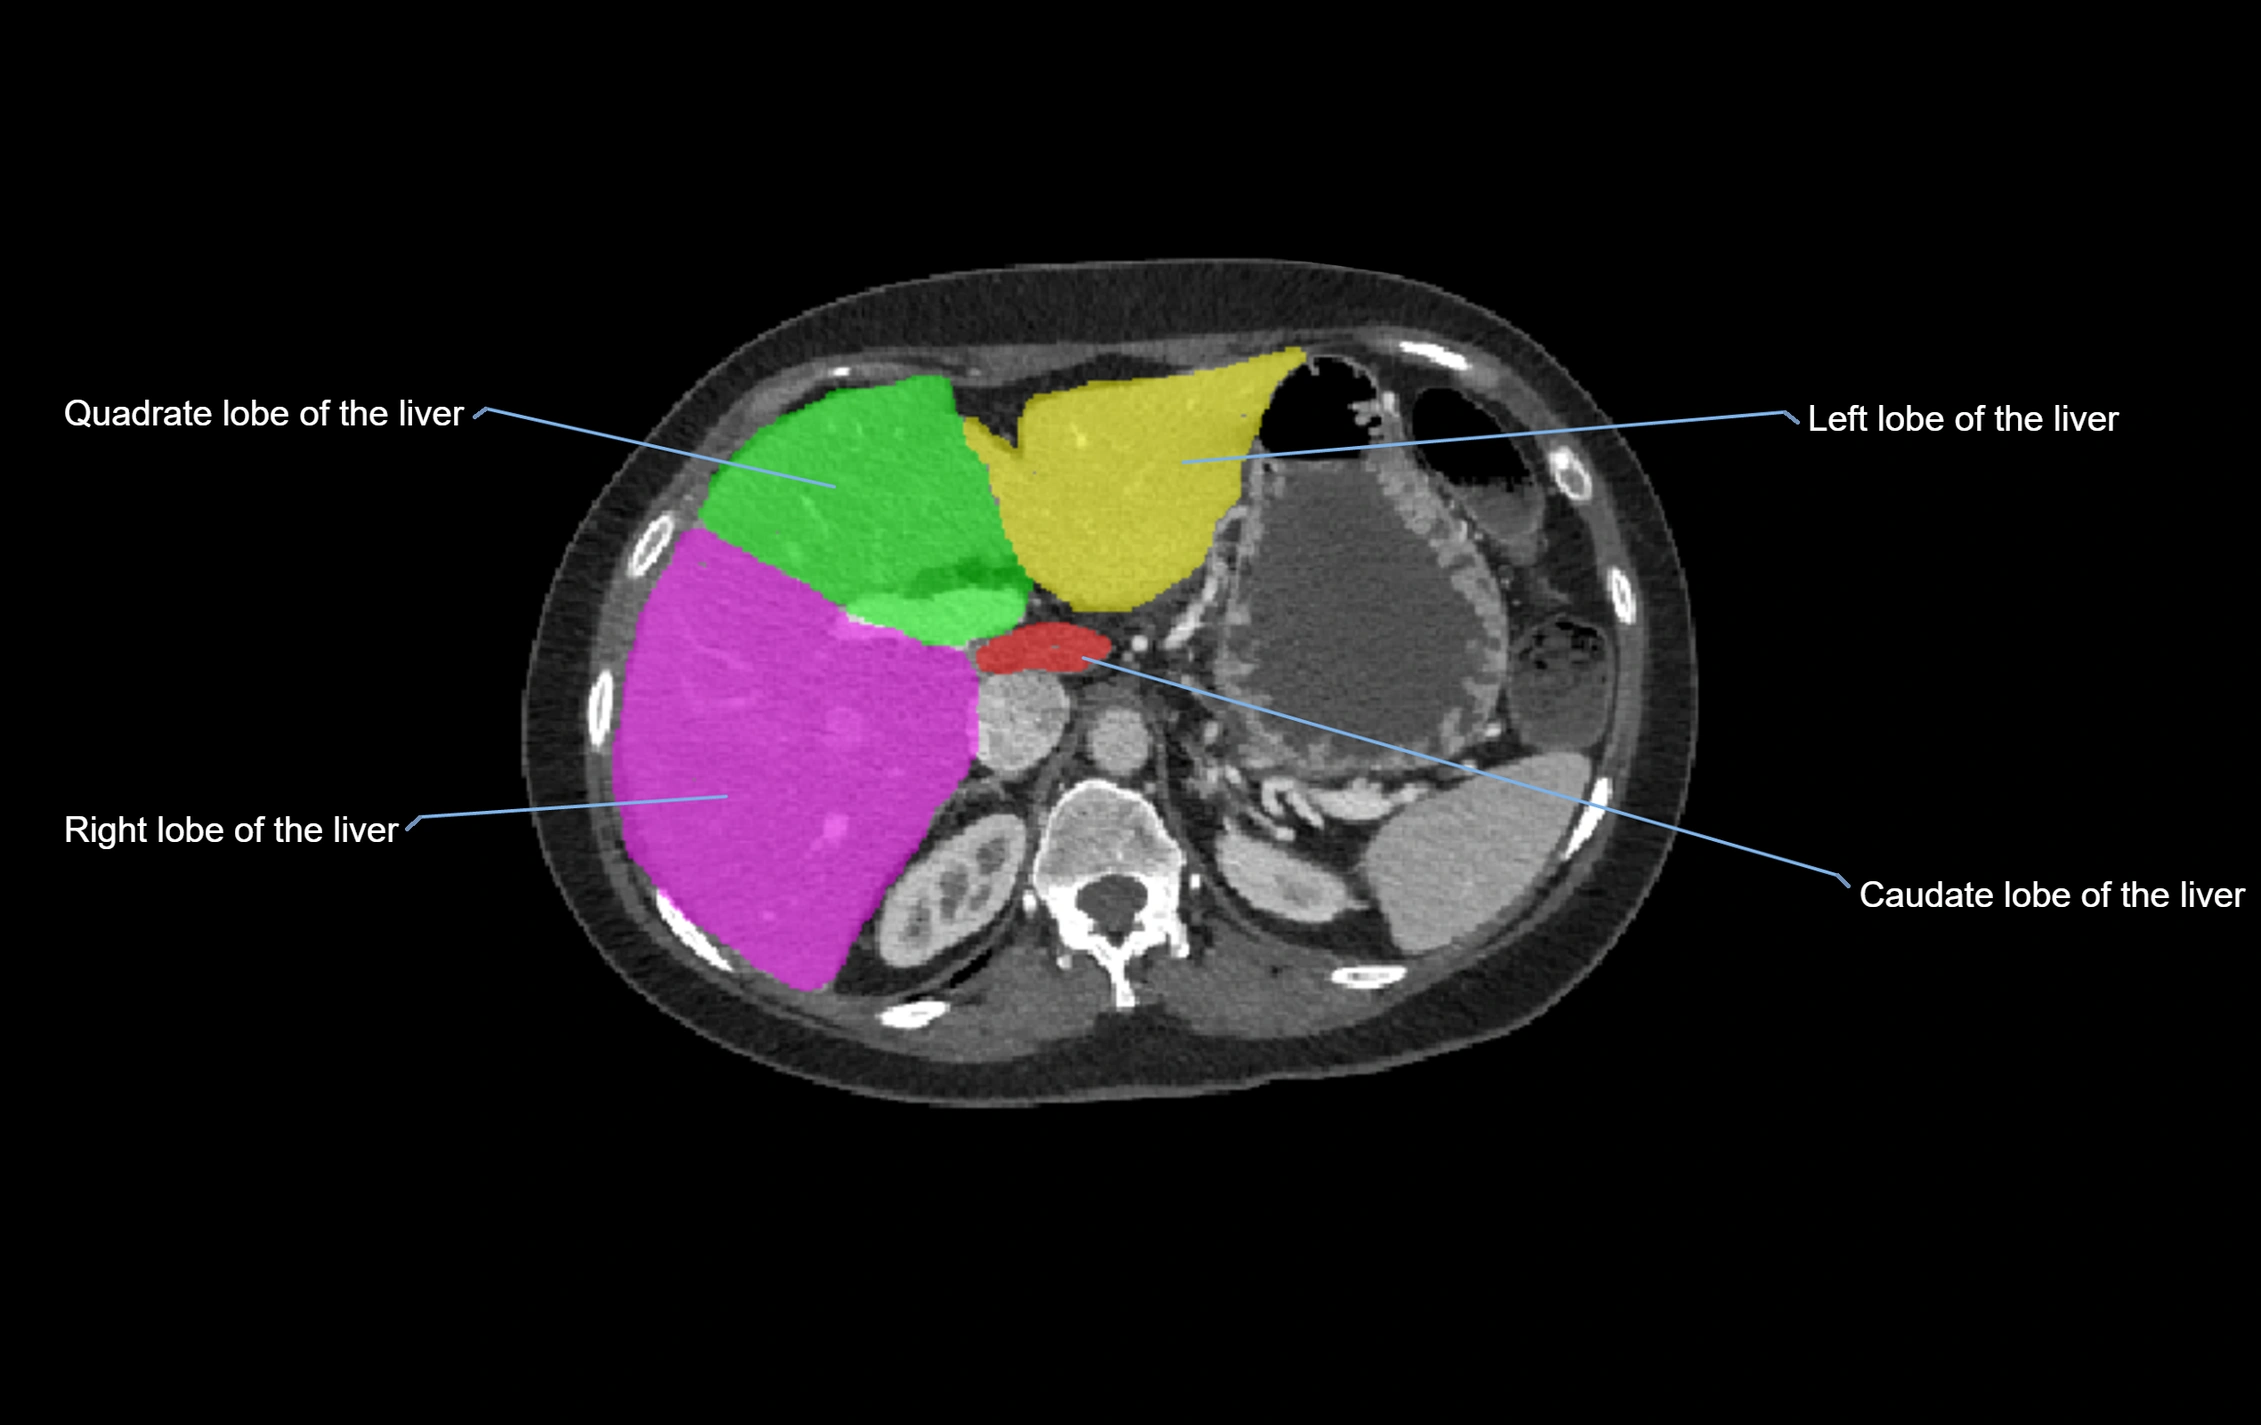

Caudate lobe of liver

The caudate lobe of the liver is a distinct anatomical subdivision of the liver, designated as segment I in Couinaud’s classification. It lies on the posterior surface of the liver, between the fissure for the ligamentum venosum (left boundary) and the groove for the inferior vena cava (IVC) (right boundary). Superiorly, it is related to the posterior liver surface, and inferiorly it is separated from the left lobe by the porta hepatis.

The caudate lobe is unique because it receives dual portal venous and arterial inflow from both the right and left portal veins and hepatic arteries. It also has independent venous drainage directly into the IVC via multiple small hepatic veins, unlike other lobes that drain through the three main hepatic veins.

This anatomical autonomy makes the caudate lobe especially significant in liver surgery, transplantation, and hepatic venous outflow obstruction syndromes (e.g., Budd–Chiari syndrome). Enlargement of the caudate lobe is a characteristic imaging feature in chronic liver disease and cirrhosis.